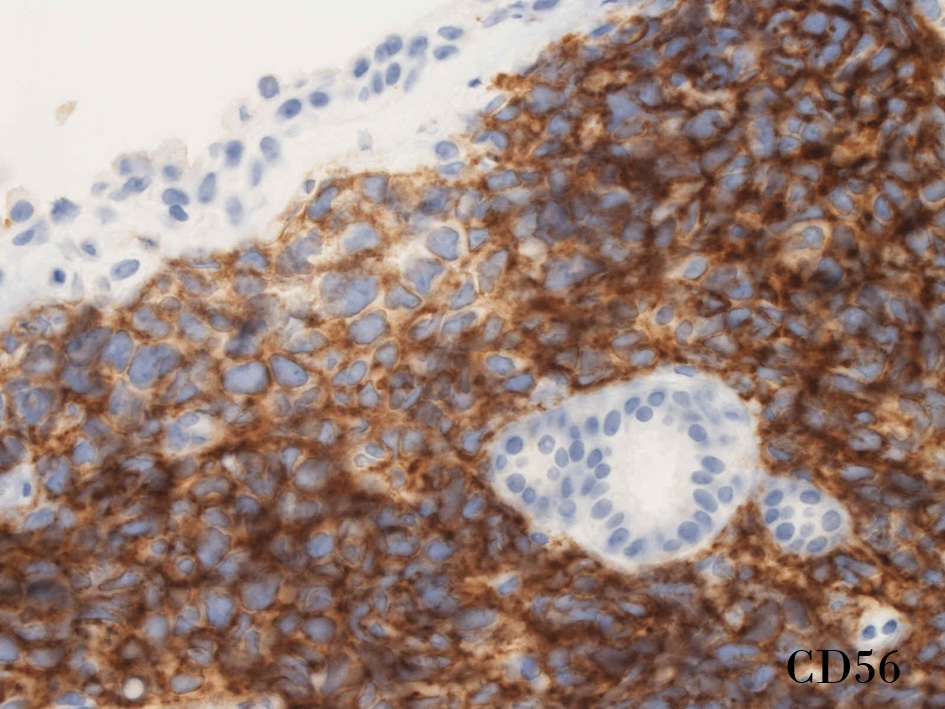

CD56CD56S-100

small round cell tumorの中でrhabdomyosarcomaは腫瘍細胞に種々の抗原が陽性となるため診断を誤ることがあり注意が必要である*1

*1 Bahrami A, et al., Aberrant expression of epithelial and neuroendocrine markers in alveolar rhabdomyosarcoma: a potentially serious diagnostic pitfall. Mod Pathol. 2008 Jul;21(7):795-806. Epub 2008 May 16. PMID:1848799199